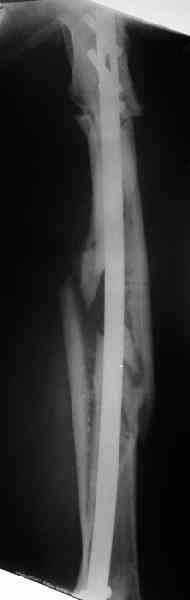

Уважаемые коллеги! Пришел на консультацию вот такой больной (первые 3-и рисунка). Травма автодорожная, апрель 2006г. Лечился консервативно, вытяжение и гипс. Через пять месяцев стал ходить. Укорочение бедра 6 см. 26 февраля 2007г. оступился, упал. Прооперирован в г.Баку - наложен стержневой аппарат. Ходит с костылями, наступая на левую ногу. Мы попросили что нибудь из ранних снимков. Принес рентгенограммы перелома (рис. 4,5). Посмотрели, наснимали сами (рис. 6-10). Похоже, что нет сращения нигде. Хотелось - бы обсудить следующие вопросы:1. дальнейшая тактика - реостеосинтез или подождать (ослабить аппарат, дать нагрузку и т.д.)?2. если реостеосинтез - то чем и как? Юрий Алексеевич Булахтин

Лучше бы закрытый интрамедуллярный, конечно.

Надо делать чрескожную подвертельную остеотомию, чтобы получился открытый клин. Проблемы будут и с формированием канала, надо развертки типа наших. Был как-то похожий случай, сделали одномоментно, сняли аппарат 5-месячый на столе, заштифтовали с подвертельной остеотомией (в приложении).

Можно все коррекции сделать и в аппарате, и потом заштифтовать, тогда останется только одна проблема формирования канала.

Если только аппарат стабилен, мне кажется, можно продолжить стабилизацию. При таком сложном переломе важно достичь консолидации в области диафиза. Варус в подвертельной области можно откоррегировать позже. Есло позволяет конструкция внешней опоры и позволяет состояние мягких тканей - усилить базу в проксимальном фрагменте и попытаться устранить деформацию в процессе, хотя это маловероятно. желаю успеха. Анатолий